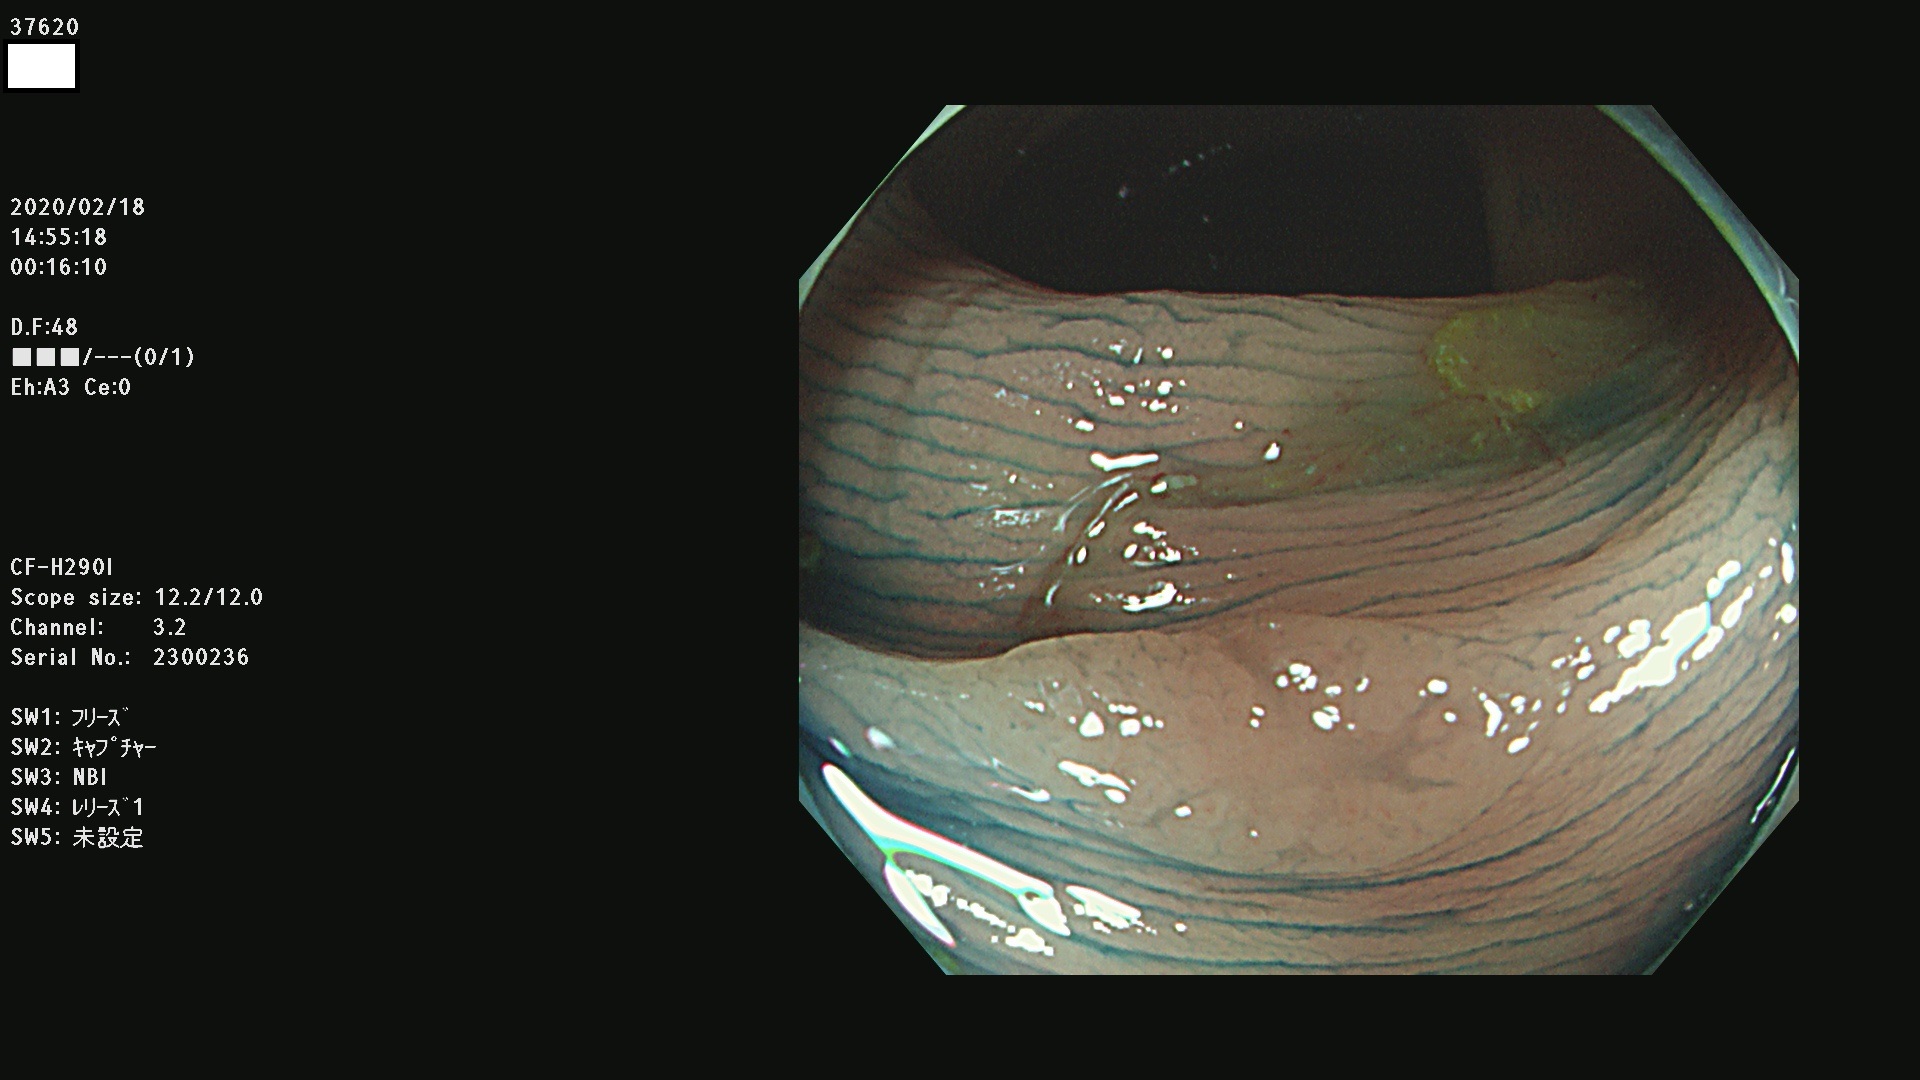

37600 37601 37602 37603 37604 37605 37606 37607 37608 37612 37614 37616 37618 37619 37620 37621 37622(SSAPのみ) 37623(SSAPのみ) 37624 37626 37627 37628 37629 37632 37633 37635 37636(SSAPのみ) 37639 37640 37641 37642 37643 37644 37647(SSAPのみ) 37648 37649 37650 37652 37653 37655 37657 37659 37660 37662 37664 37666 37668(SSAPのみ) 37670 37671 37672 37676 37677 37678 37679 37680 37682 37684 37685(SSAPのみ) 37686 37687 37688 37689 37690 37691 37692(SSAPのみ) 37693 37694 37695 37696 37697 37699

発見困難で危険性の高い平坦型病変(上記100名より抽出)